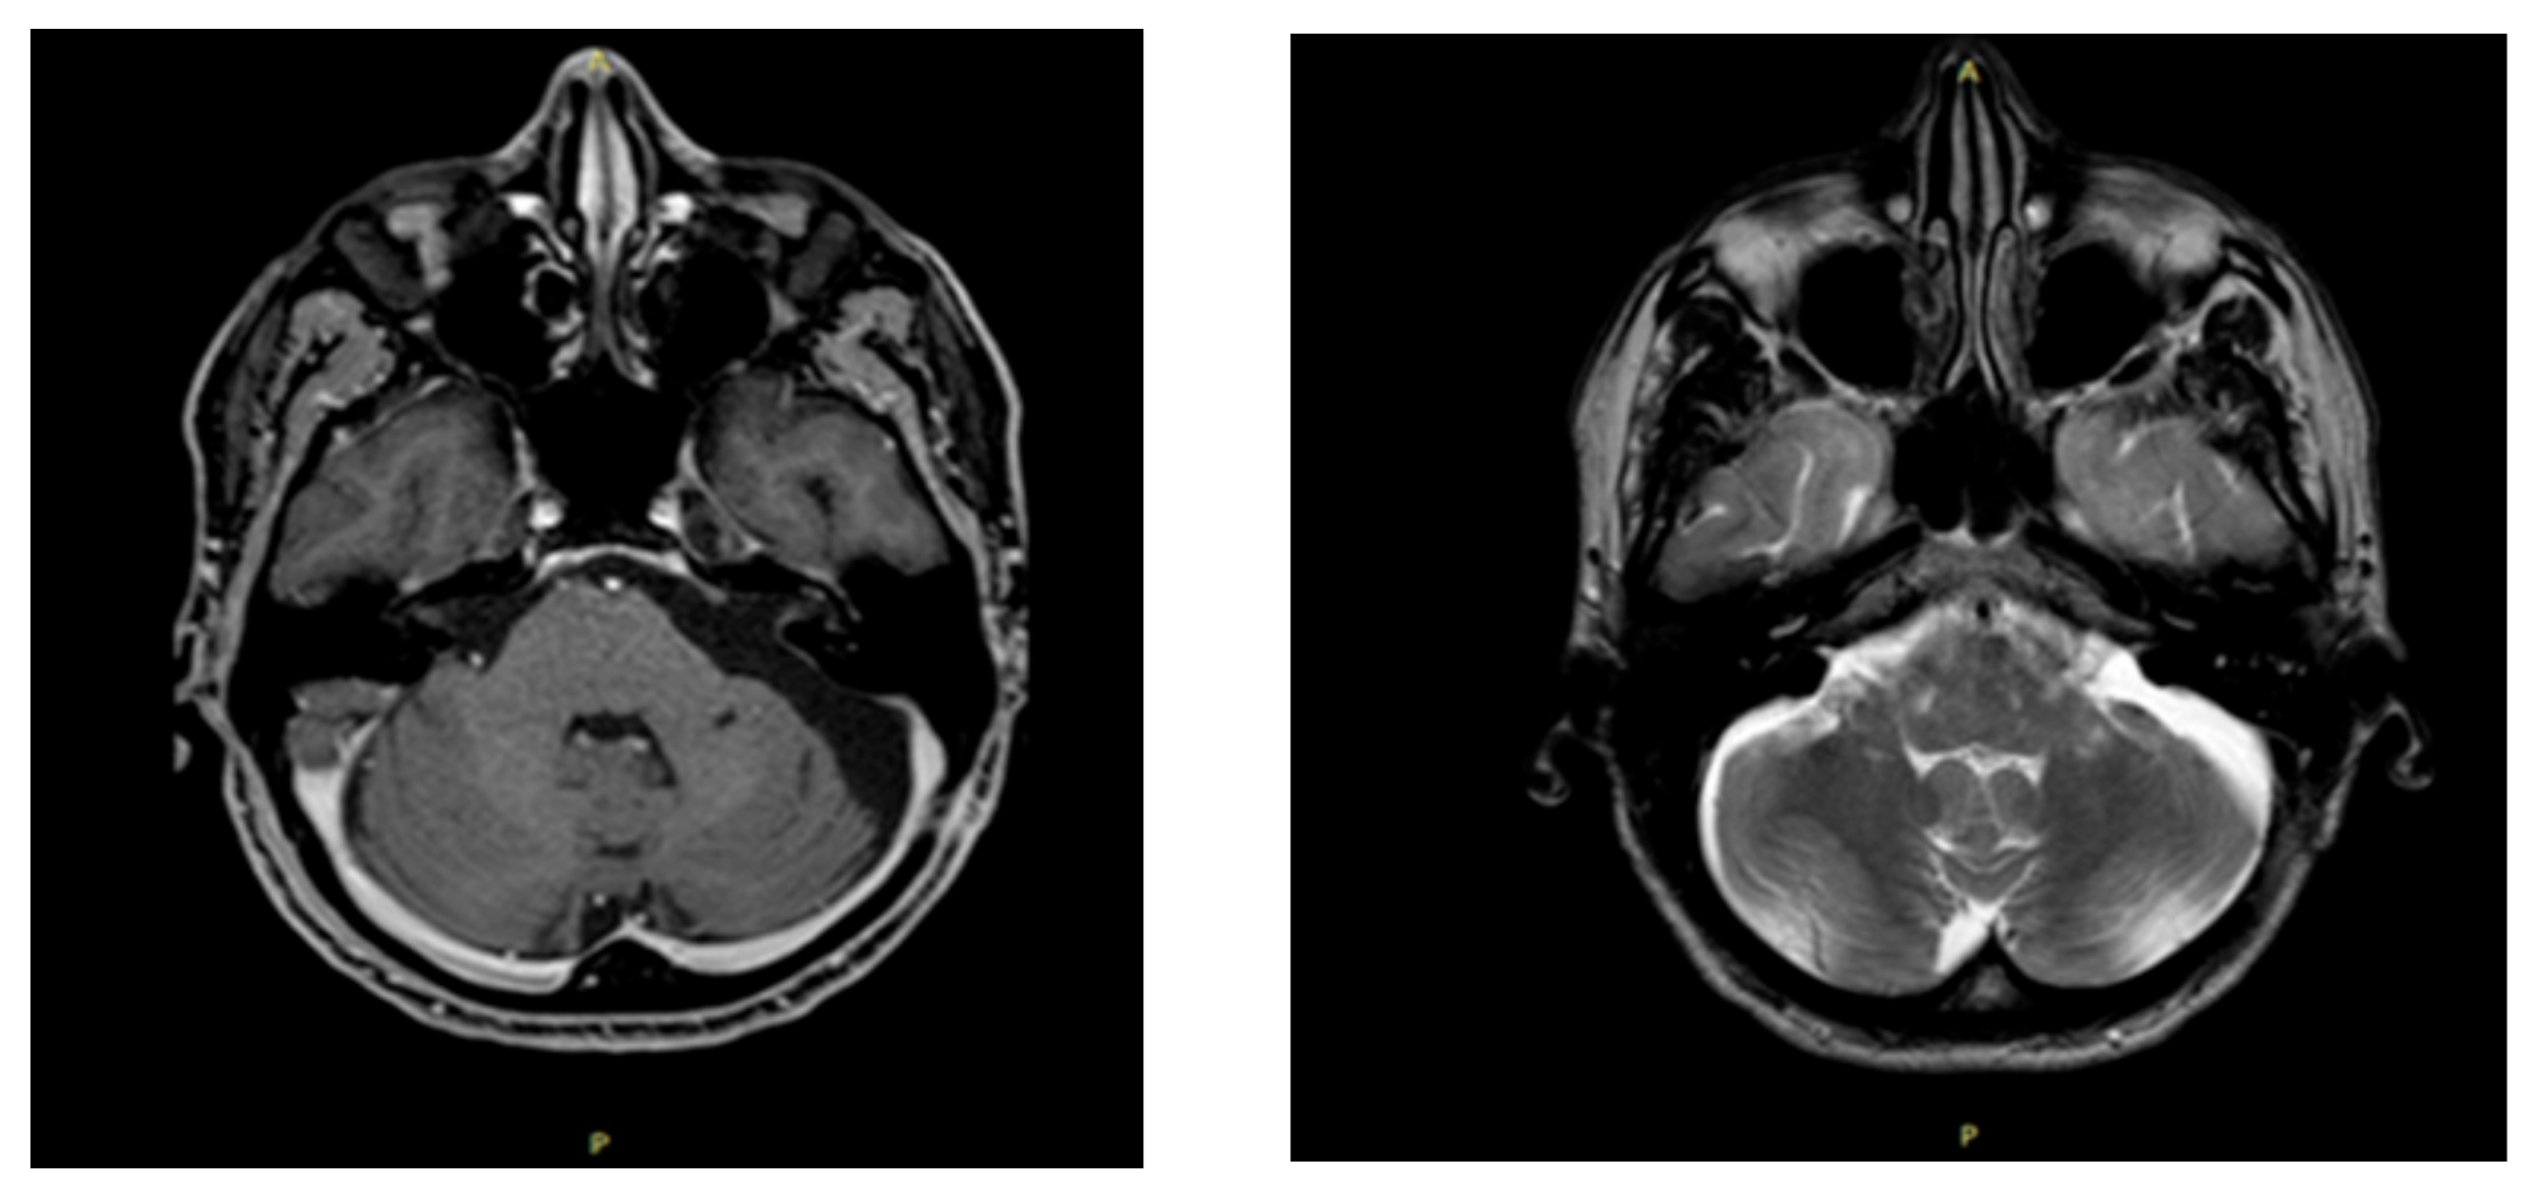

The neurosurgeon prescribed an MRI with contrast medium (gadolinium) and an electromyography. The MRI revealed an “area of altered signal (diameter of 5.2 × 2.6 × 3 cm) at the level of the left cerebellopontine angle, which had a coarse fibrotic sprout and micro sprouts inside, with a chaotic distribution. The intralesional fluid content was not very homogenous and had fine corpuscles. This cystic-type formation significantly compressed the brain stem, which was displaced to the right of the midline, and pushed the angle of the ipsilateral cerebellar peduncle in a postero-medial direction, deforming it. Furthermore, the formation compressed the left-anterior part of the pons, close to the basilar artery” (Figure 3). The electromyography/elettroneurography examination showed severe axonal damage along the motor fibers of the left accessory (XI) and suprascapular nerves. In particular, the traces at maximum effort are defined as “interferential” on the deltoid muscles and biceps brachialis, while they are “poor-intermediate” on the supraspinatus and trapezius muscles. Such assessment also showed an initial slowdown in the distal motor latency and in the sensory conduction velocity of the left median nerve due to antidromic recording from the third finger of the left hand. The sensory and motor neurography of the left radial and ulnar nerve was within the limits and the neurography of the left musculocutaneous nerve was also within the limits, while the amplitude of the compound muscle action potential of the left accessory nerve was reduced compared with the contralateral. Therefore, the neurosurgeon recommended surgery.

Figure 3. MRI scans before surgery. Notes: T1 weighted sequence (left) and SE-T2 weighted scan (right). Cystic type formation compressing the brain stem and deforming the angle of the ipsilateral cerebellar peduncle.